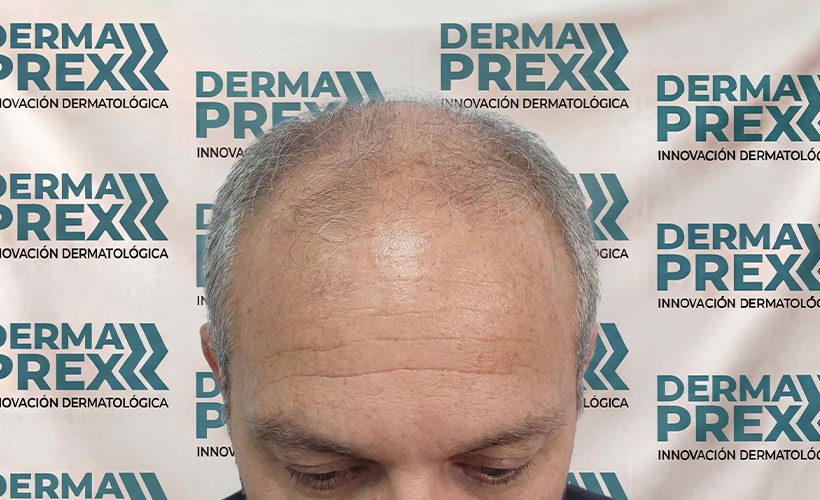

Entender, antes de Suplementar

Los cambios capilares pueden tener múltiples factores. La orientación adecuada marca la diferencia.

Resultados reales, confianza real

Cada tratamiento capilar cuenta una historia… y estas son las que más nos inspiran.

En esta sección encontrarás casos reales de personas que decidieron dejar de improvisar y empezar un tratamiento adecuado para su tipo de caída, logrando mejoras visibles en el crecimiento, fortalecimiento y salud de su cabello.

Fortalece tu cabello desde la raíz

Ayuda a estimular el crecimiento capilar, mejorar la densidad del cabello y fortalecer las zonas con pérdida progresiva, como entradas o coronilla.